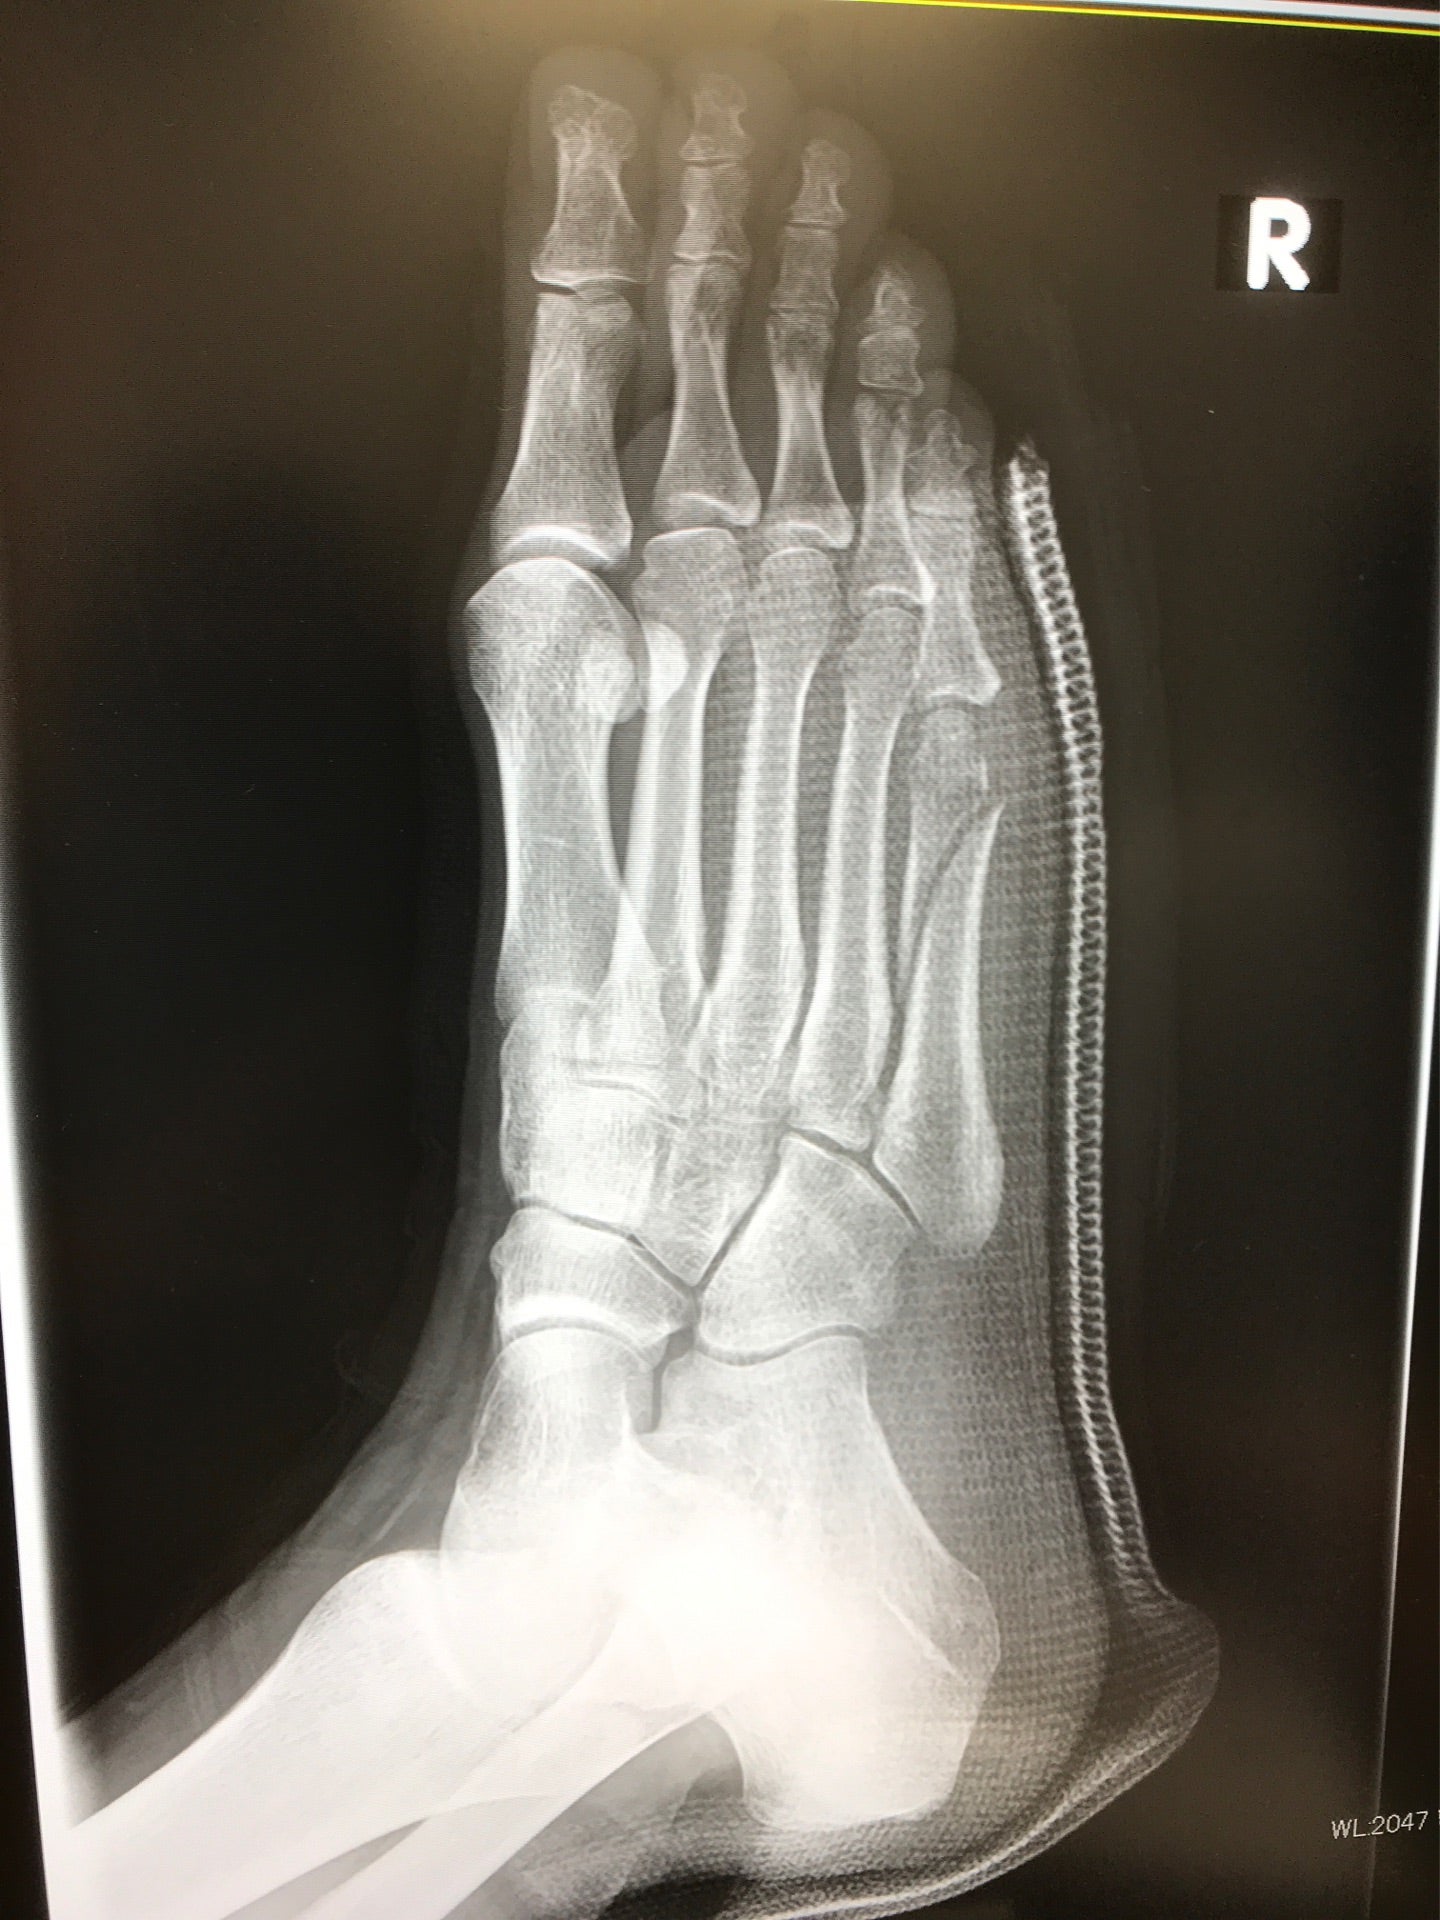

ももたんももたん6年前完治まで3か月はかかると予想。( ; ; )松葉杖でいると、大阪人めっちゃ優しい!知らんおっちゃんとかおばちゃんとめっちゃ話した!京都人シーン…って感じが浮き彫り。京都人やけど 笑